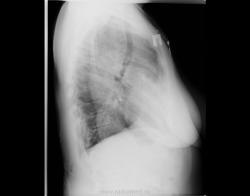

При профилактическом исследовании у женщины 75 лет выявлены изменения в легких и средостенье. Выполнена КТ. Ваше мнение, коллеги?

Ну, слева на верхушке - не провокация.

Почему провокация?! У меня что, имидж такой? о провокациях я так сразу и пишу в заголовке... Нет здесь ни провокации, ни загадки. Действительно, ахалазия кардии, пневмофиброз в легких, по-видимому метатуберкулезный. А случай мне показался интересным, потому как эта ахалазия имеет 50 лет анамнеза без лечения